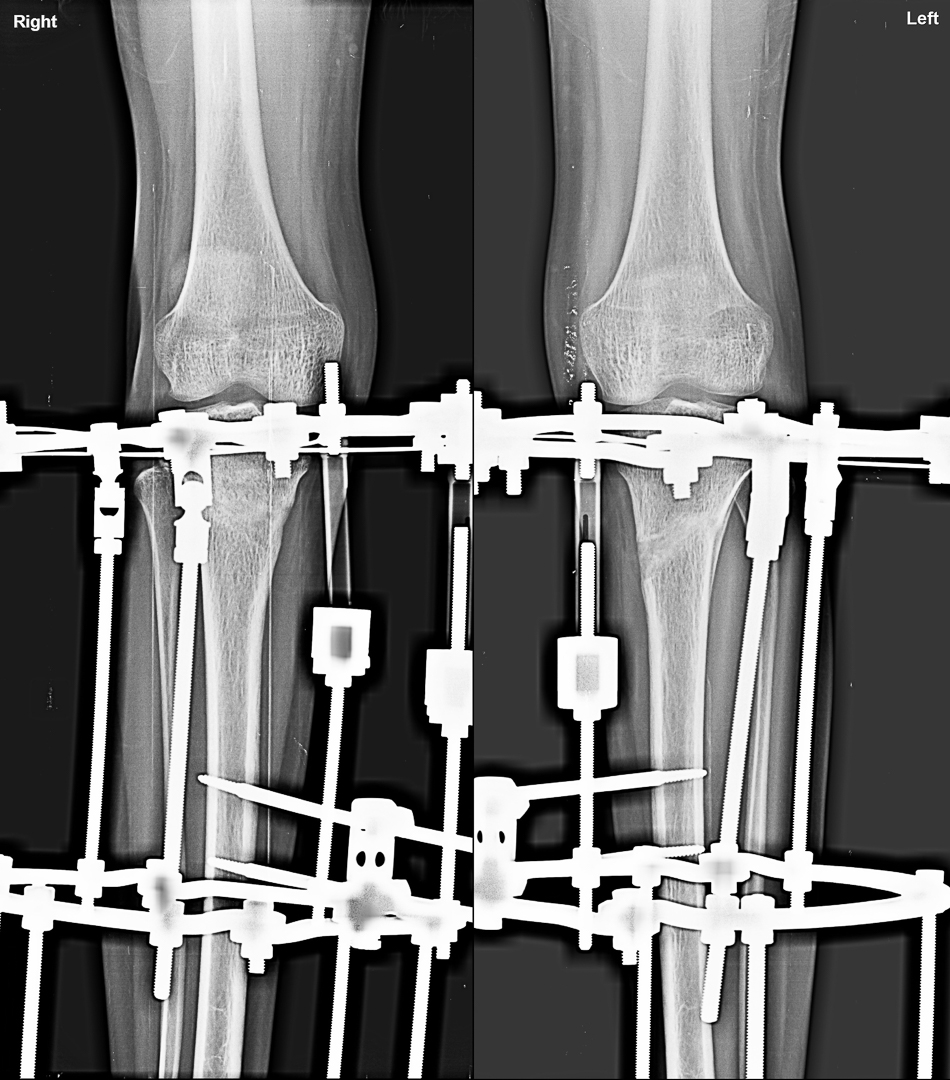

Genu Varus corrected by Osteotomy and gradual correction with Ilizarov

Osteotomies is required in patient where growth of bone stopped further or very sever deformity where growth modulation will unlikely to correct that much deformity. Osteotomy can fixed by plate or external fixater system

Gradual correction by corticotomy and bone transport by LRS System/ ilizarov.